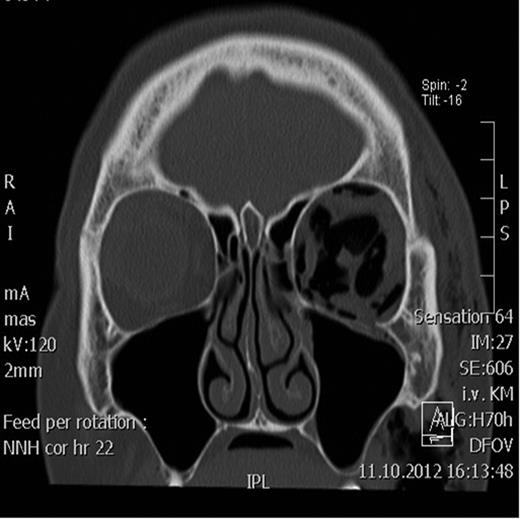

Coronal CT scan showing the retrobulbar emphysema prior to decompression.